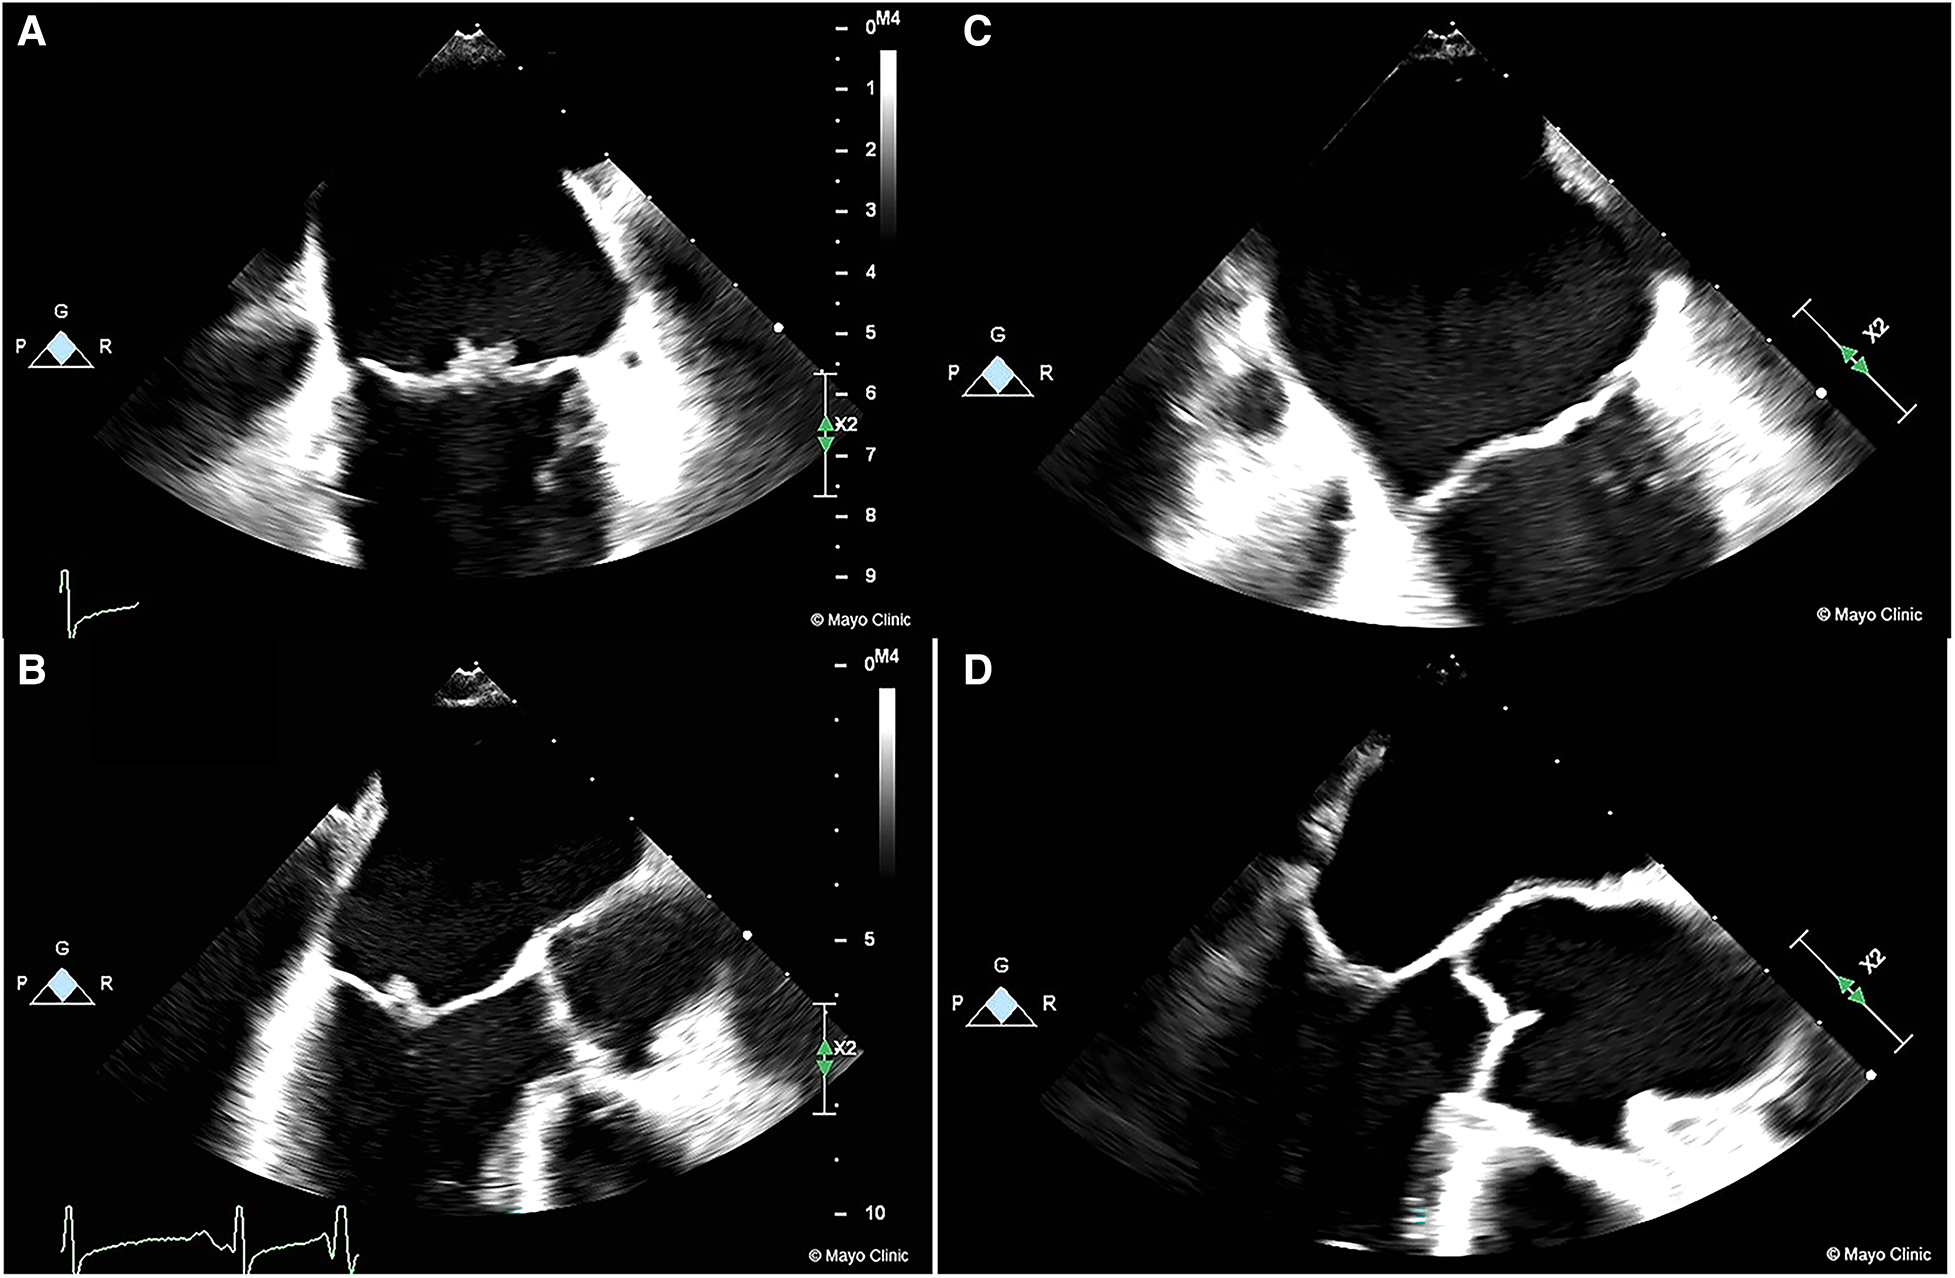

After careful review and consideration by the multidisciplinary team and shared-decision making with the patient, a decision was made to transition the patient to parenteral anticoagulation immediately due to the high risk of recurrent embolization in the setting of apixaban failure. The patient was started on a lower dose of enoxaparin initially (40 mg BID subcutaneous) due to the concern of hemorrhagic transformation. The dose was titrated up to 1 mg/Kg twice daily (70 mg). Anti-Xa levels were checked 4 h after the 4th dose and demonstrated therapeutic levels of 1.01. A repeat CT of the head was performed after 2 therapeutic doses (70 mg) of enoxaparin to assess for hemorrhagic conversion of infarcts. She was discharged on therapeutic low molecular weight heparin (LMWH) therapy, and a TEE repeated after 4 weeks of therapy showed complete resolution of the NBTE (Figure 1, Supplementary Video S3).

Figure 1

Images of NBTE seen on TEE at presentation prior to LMWH treatment (1A/1B) compared to TEE done 4 weeks after treatment showing complete resolution (1C/1D).